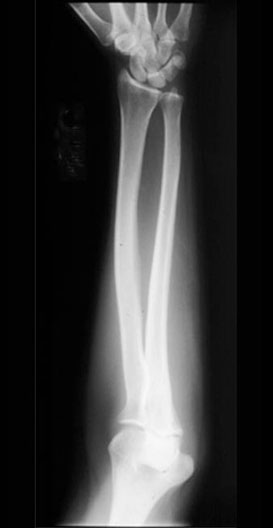

Forearm X-Ray

Roll mouse over image to display labels.

1. Styloid process of radius

2. Radius

3. Radial tuberosity

4. Radial head

5. Lateral epicondyle

6. Styloid process of ulna

7. Head of ulna

8. Ulna

9. Olecranon

10. Medial epicondyle

11. Humerus